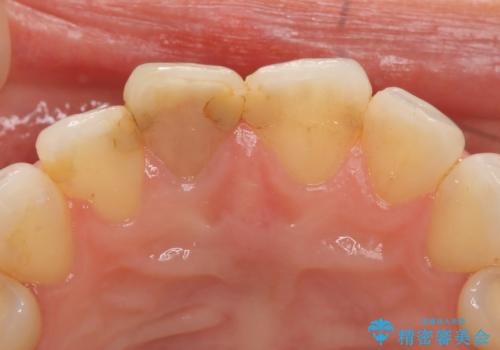

- 右上1番目の歯の変色が気になると来院された方の症例です。

検査の結果、右上1の歯は失活(歯の神経が死んでいること)していたため根管治療を行いました。

その後オールセラミッククラウン(スペシャル)による補綴を行いました。

なお隣在歯の樹脂は今後治療していく予定です。